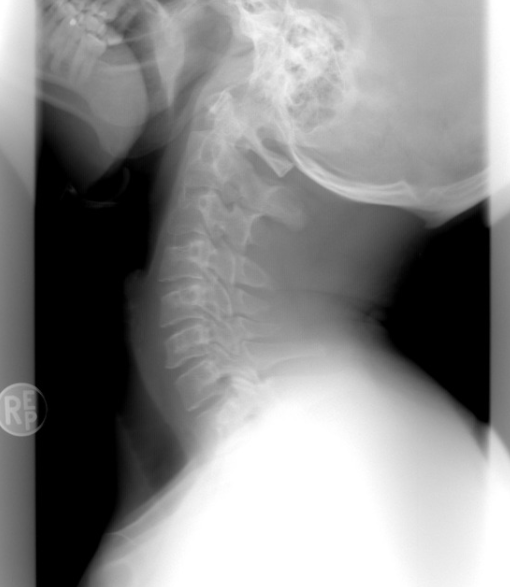

아무래도 꼬리뼈가 아프면 허리보다는 엉덩이 쪽을 의심하기 마련인데, 전혀 그렇지 않다. 디스크 등이 관련되어 있는 병이더라도 꼬리뼈가 아픈 이유 중 하나가 될 수 있다. 이런 척추질환의 가장 대표적 이유는 노화로 인한 움직임의 감소와 더불어 운동량의 부족으로 이런 결과들을 초래하게 되는 것이다. 만약 척추질환이 있는데 방치했다가는 나중에 더 큰 치료비와 시간을 들여야 할 수 있다는 점을 명심하자.